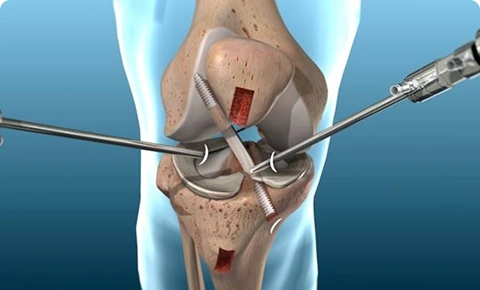

Arthroscopic knee surgery illustration showing ligament repair with surgical instruments.

Arthroscopy Surgery

Experience the benefits of minimally invasive care. Dr. Easwar’s expertise in arthroscopy, from him fellowship, means less pain, smaller scars, and faster healing.